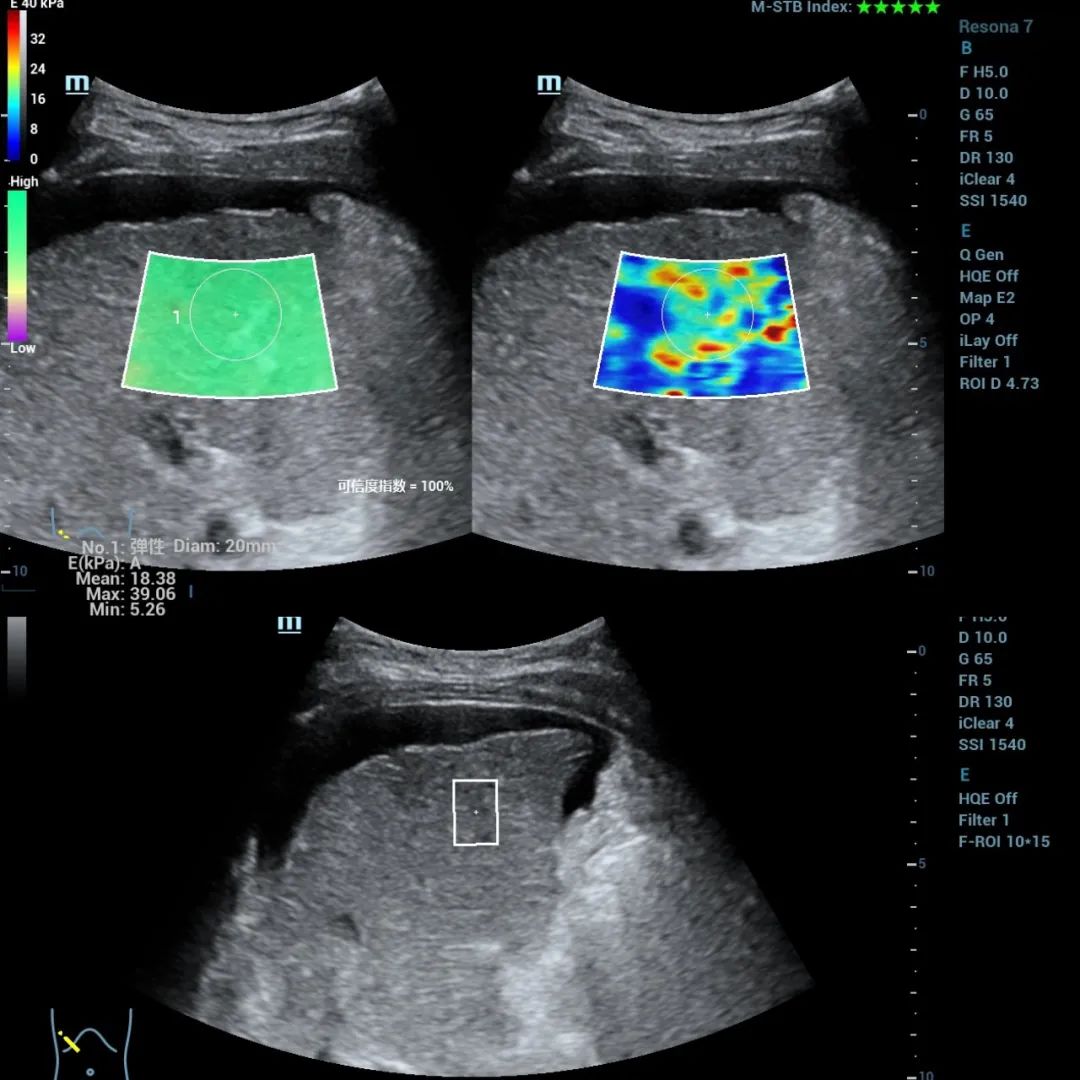

现在随着超声技术的发展,超声弹性的应用已经得到了临床普遍应用和认可,并被各大国际指南所推荐。

超声弹性技术可以对肝脏组织进行硬度测定,以协助排除有无肝硬化的存在,因其无创、可重复性好,已广泛应用于临床诊断和疾病随访等。

超声弹性技术解决方案

临床上应用瞬时弹性成像进行肝脏硬度测定的同时也可以通过对肝脏脂肪衰减系数的测定来定量反映肝脏脂肪含量。可谓一举两得!